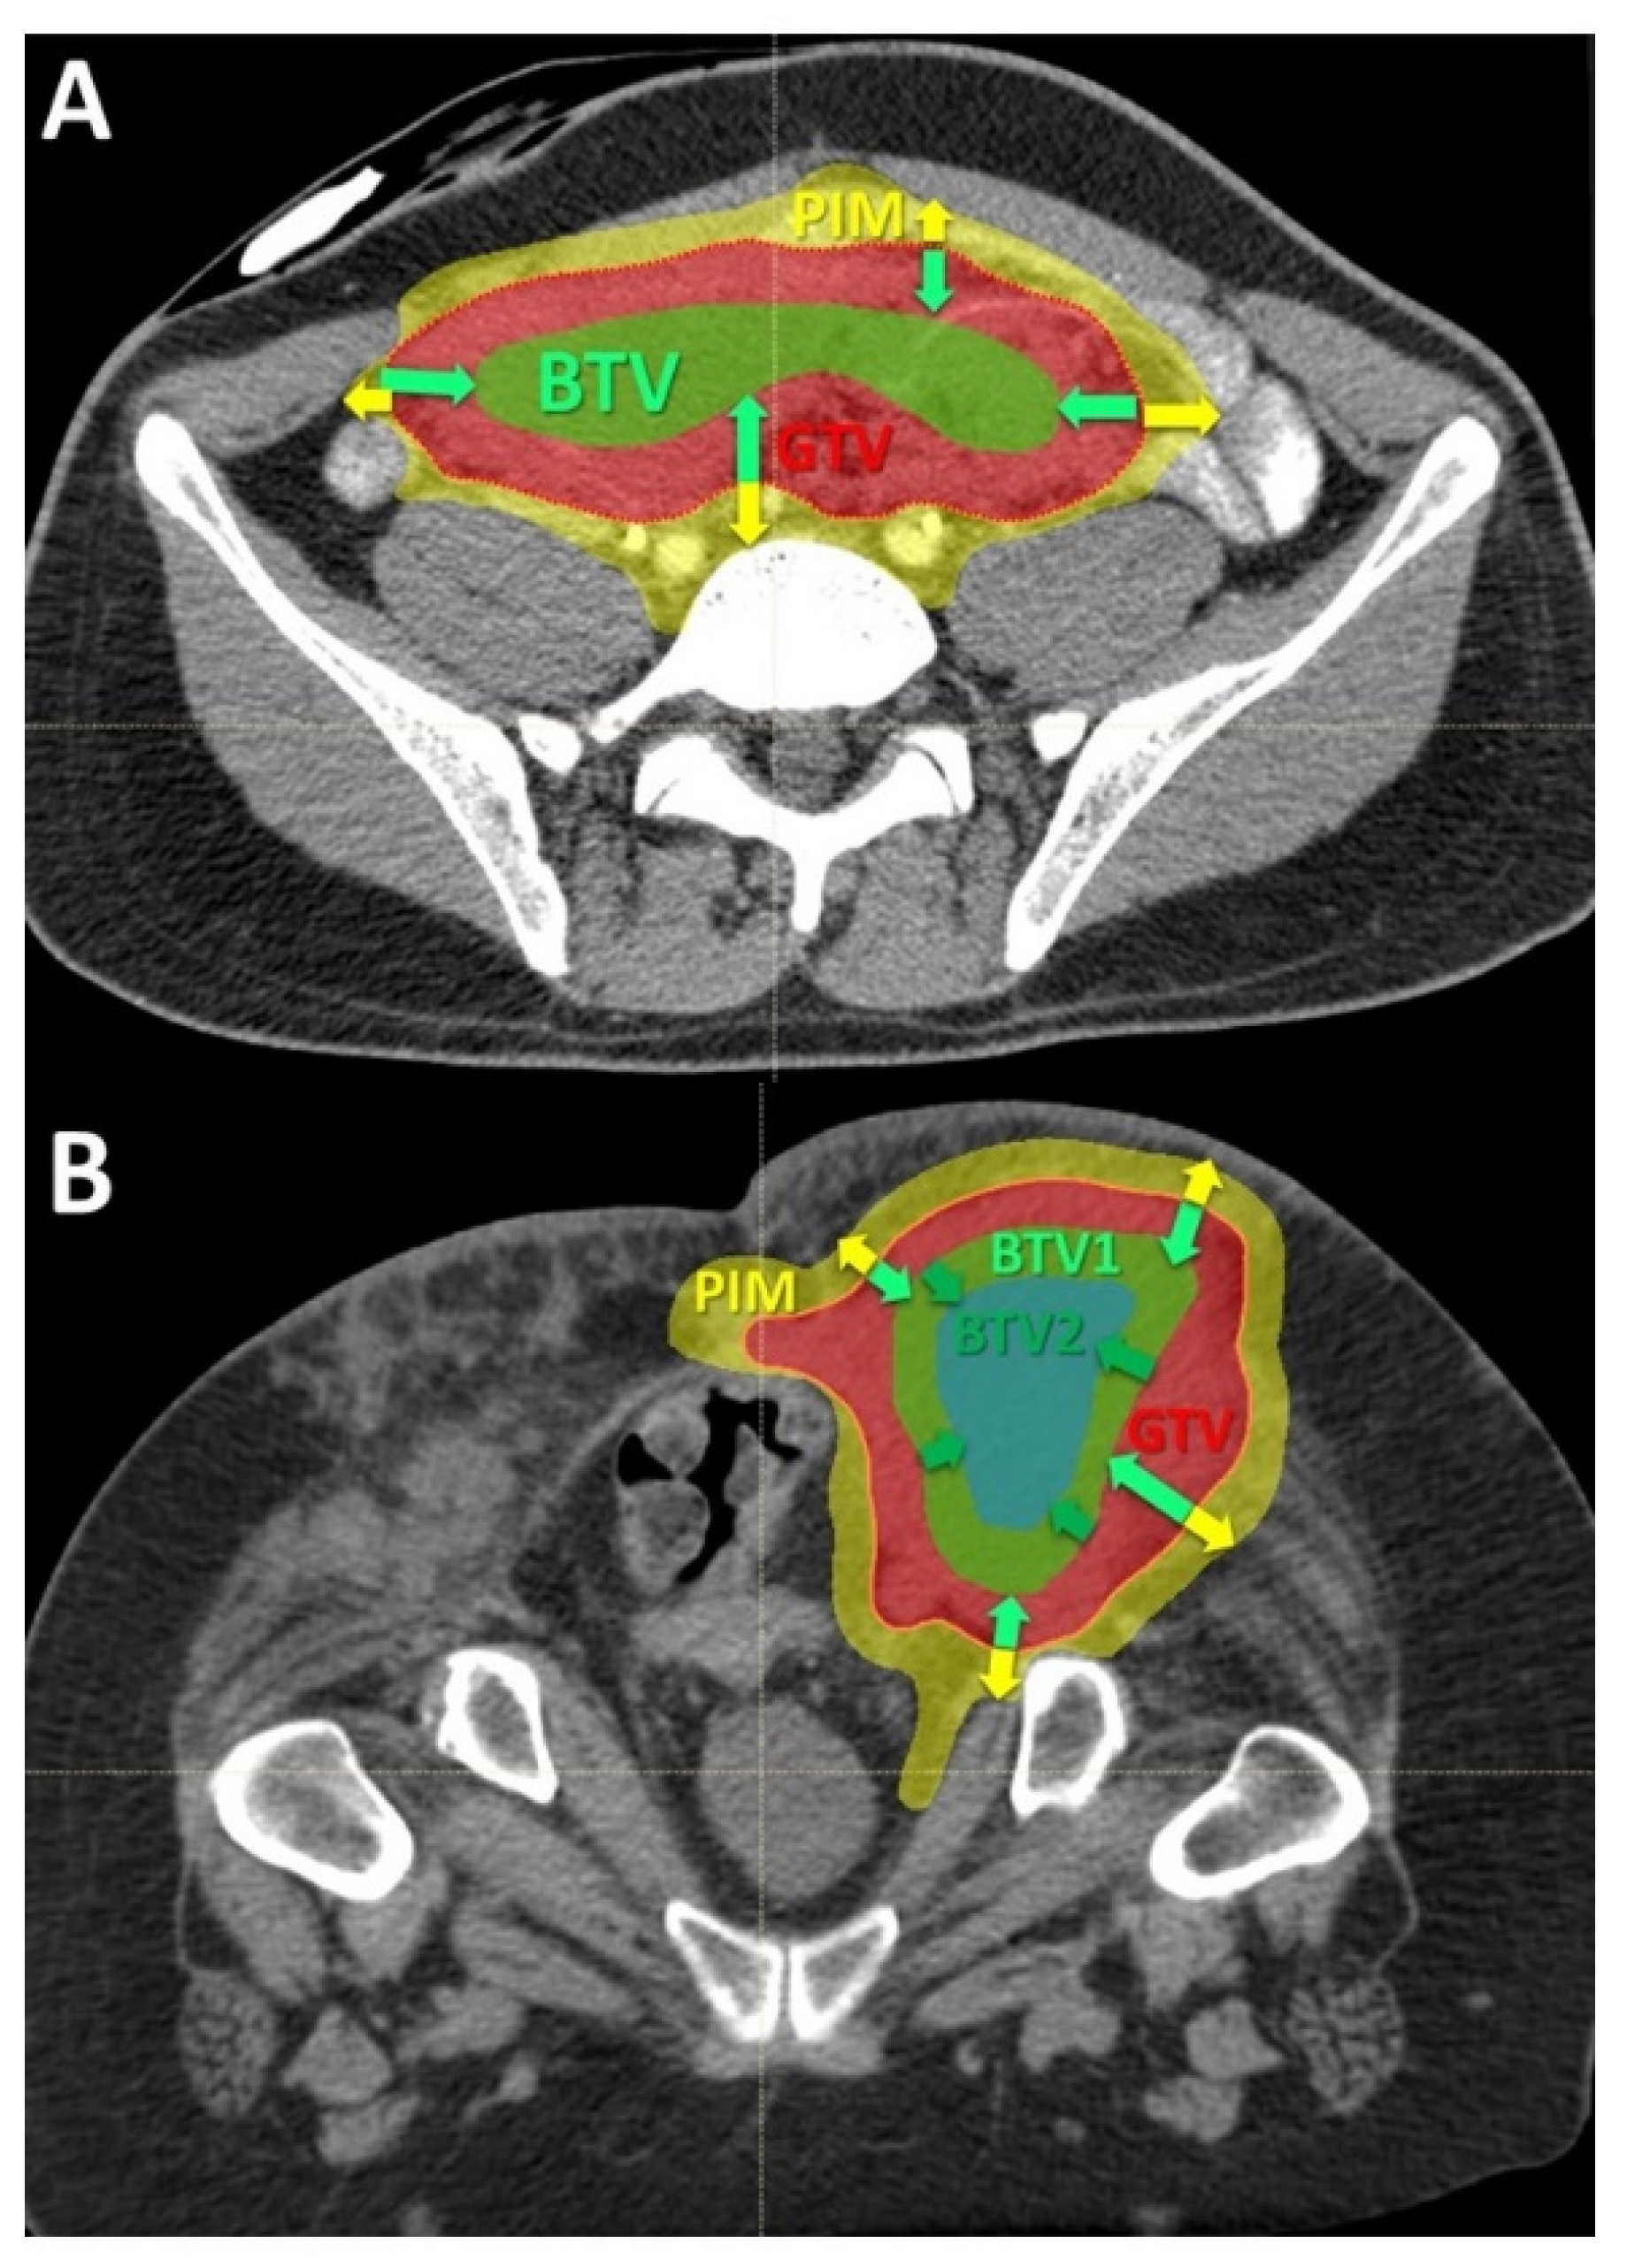

Volumes definition: The targeted internal partial tumor volume is termed “Bystander Tumor Volume” (BTV). Its delineation was adopted from previously published studies on photon-based SBRT-PATHY [7,8]. Since in those series the BTV corresponded on average to the centrally located approximately 30% of Gross Tumor Volume (GTV), in this study it was created by subtracting 1cm from the GTV surface in all directions until reaching 30% (+/−3%) of the GTV volume (Figure 2). No additional margins, neither for the Clinical Target Volume (CTV) nor for Planning Target Volume (PTV), were applied to the BTV since the objective of this treatment was to irradiate a tumor sub-volume in order to effectively spare the peritumoral immune system cells. No hypoxia-specific tumor imaging, which is planned for future patients, was utilized in this present group. However, the majority, if not all, of the hypoxic tumor segments were likely covered by the BTV volume since in all cases the central, necrotic and perinecrotic tissues were included in the BTV.

Once the BTV was defined, the PIM was created (Figure 2A,B). The PIM, containing the loco-regional infiltrating immune system cells as the mediators of the non-targeted radiation effects, was considered an OAR (Organ At Risk). The PIM was created by adding a uniform 1 cm margin to the GTV and then subtracting the same GTV to create “a ring” that surrounds the GTV. The goal of treatment planning was to keep the dose within the PIM as low as reasonably achievable but considering the following dose constraints as the planning objective: Dmean < 6 Gy, D20 < 0.5 Gy, D30 < 1 Gy and D50 < 3 Gy in three fractions. Additionally, all nearby regional vascular supply and lymph node stations were included if they were within the 2 cm-distant areas from the GTV.

To deliver sufficiently high and possibly heterogeneously distributed radiation dose at the level of the targeted BTV. The intended dose was in the order of 10–15 Gy per fraction. In order to address heterogeneity in radiation dose delivery, dose-gradients were created within the BTV, by creating an additional BTV (BTV2) within the former BTV (BTV1) by subtracting 5 mm from the BTV1 surface in all directions whenever tumor volume would permit it (Figure 2B and Figure 3B).

Achieving the BTV prescription goal was subordinated to the possibility of creating a sufficiently sharp dose fall off between the BTV surface and the GTV surface surrounded by the PIM and was proportional to the thickness of peripheral tumor tissue in between the BTV and GTV surfaces. Treatment plans were calculated to deliver 30–36 Gy in three consecutive fractions (10–12 Gy per fraction) to the BTV1, and 36–45 Gy (12–15 Gy per fraction) to the BTV2 so that at least 95% of the BTVs received as minimum 95% of the prescription dose. The choice of prescribing the fractional doses was driven by PIM-sparing: 12 Gy to the BTV1 with 15 Gy to the BTV2 were preferred if allowing planned PIM-sparing which was easier to achieve in particularly large tumors. Otherwise, the fractional dose was reduced to 10 Gy to the BTV1 with 12 Gy to the BTV2 to lower the dose received by PIM. In those patients in whom neither of the two goals was possible, only one BTV (BTV1) was created and treated either with 12 Gy × 3 or 10 Gy × 3 (Figure 2A and Figure 3A). Reported doses in Gy are RBE-weighted doses calculated from the physical dose using the LEM model for carbon ions [22] while for protons a fixed RBE of 1.1 was assumed.

Figure 2. Delineation of the Bystander Tumor Volume (BTV) and Peritumoral Immune-Microenvironment (PIM): (A) the figure shows the principles of the target delineation for Particle-PATHY treatment. After the Gross Tumor Volume (GTV, red dotted line) has been defined, the BTV-partial tumor volume (green line) as the target for PATHY irradiation has been created by subtracting 1 cm from GTV surface in all directions reducing the GTV volume to the 30% (+/−3%). PIM (yellow line) was created by adding a uniform 1 cm margin to the GTV and then subtracting the same GTV to create “a ring” that surrounds the GTV; (B) In those patients affected by particularly large tumors two tumor sub-volumes BTV1 and BTV2, respectively, were delineated whereby the BTV2 was created by subtracting 1 cm from BTV1 (or 2 cm from GTV surface) in all directions.